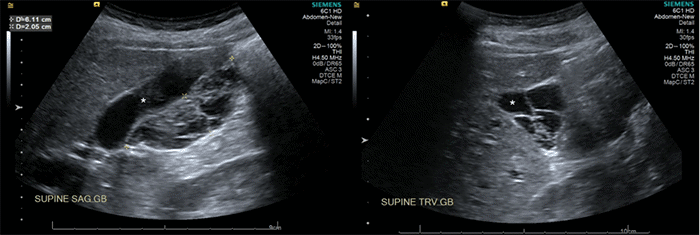

A 47-year-old woman underwent an abdominal CT scan in the outpatient setting to investigate hematuria. An incidental finding of a gallbladder mass was identified. Subsequent abdominal ultrasound revealed a 12 × 37 × 67 mm cystic lesion with avascular septations (Figure 1). Further evaluation with magnetic resonance imaging (MRI) and magnetic resonance cholangiopancreatography (MRCP) showed a high T2 signal lesion located posteriorly and medially within the gallbladder fossa (Figure 2).

Figure 1. Gallbladder Pathology. Published with Permission

Sagittal (L) and transverse (R) views: Gallbladder (*) demonstrating a cystic mass with septations